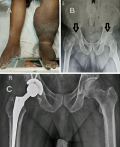

Osteonecrosis of the femoral head (ONFH) is a progressive disorder caused by vascular compromise to subchondral bone, leading to joint collapse and disability. It is associated with multiple risk factors, but its coexistence with chronic lymphatic filariasis is rarely reported. Early diagnosis and management are crucial to prevent irreversible hip destruction. This case highlights the rare association of chronic lymphatic filariasis with bilateral femoral head osteonecrosis, the limited benefit of core decompression in advanced disease. A 52-year-old male, known case of bilateral lymphatic filariasis for forty years, presented with progressive dull aching pain in the right hip and difficulty in ambulation for one year. The pain was progressive, aggravated by weight-bearing and relieved by rest. Six months earlier, he had undergone core decompression with bone grafting, without symptomatic relief. Subsequently, symptoms worsened with functional limitation. Radiographs revealed bilateral avascular necrosis of femoral heads (R>L), and the patient underwent right total hip arthroplasty with physiotherapy rehabilitation.

Figure 1: A) chronic lymphatic filariasis of bilateral lower limb (L>R); B) pre operative Pelvic radiograph showing bilateral femoral head osteonecrosis (R>L); C) post-operative radiograph showing right total hip arthroplasty in situ